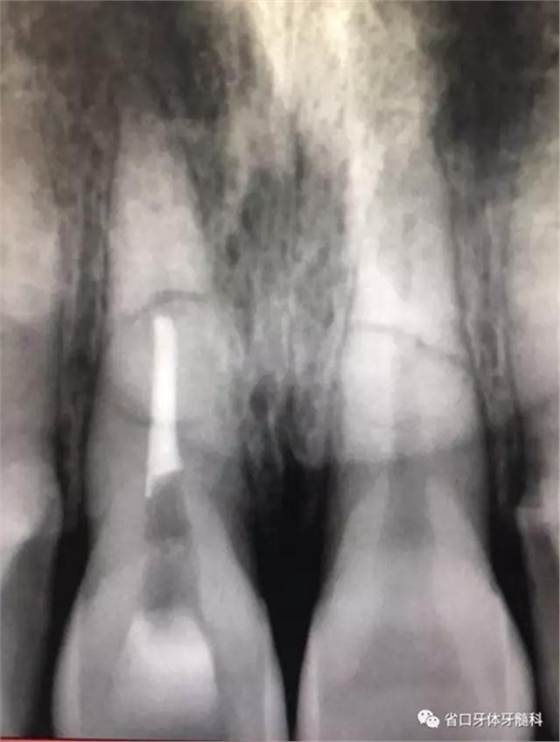

圖3:11術(shù)前CT

圖4:21術(shù)前

診斷:11、21根折(合并輕度牙槽骨骨折)